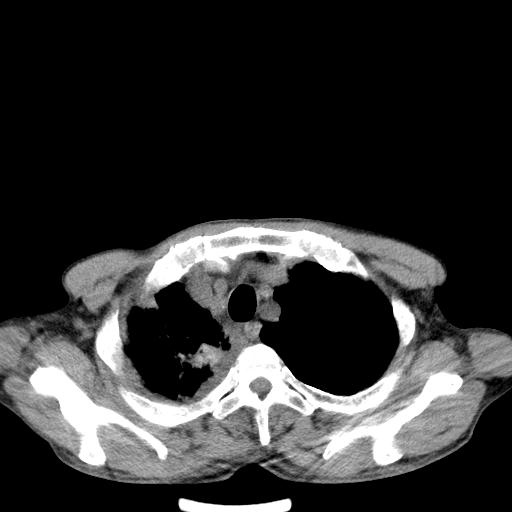

男性 75  咳嗽 一周前发热最高达39

右肺继发型tb并右侧tb性胸腔炎,右侧胸腔大量积液并右下肺膨胀不全,慢支肺气肿、多发肺大泡。建议抽胸水实验室检查并复查排除恶性在占位。

右上肺继发型肺结核,右胸腔中等量积液。

左上肺大泡。

结核的基础上有纵隔淋巴结肿大,右侧有胸水,但右侧纵隔反而窄,说明有肺有不张。

再就是右下肺有块影,和不张混合,还是不能除外肺癌。

1)右肺继发型肺结核。2)左肺胸膜下多发性肺大泡。3)右侧胸腔积液。